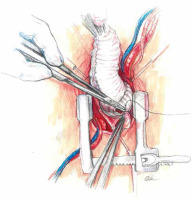

A skin incision is made over the handle of the sternum up to the 3rd or 4th intercostal space. The skin incision is usually about 5–6 cm. Its length depends on the structure of the chest and the length of the sternum. Subcutaneous tissue up to the fascia is dissected using cautery. At the level of the 3rd or 4th intercostal space on both sides, the fascia is completely dissected just above the upper edge of the sternal attachment of the rib. Then, arrow-shaped lines directed with the tip downwards are drawn from the notch of the zygomatic sternum to the designated two parasternal points. Then the breastbone is cut with an electric saw. In the next stage, thymic fat is dissected from the brachiocephalic vein. The pericardial sac is opened longitudinally and to the sides at the lower end as with a standard pericardial inverse “T” incision. On each side of the sternum, 3–4 pull-back pericardial sutures are placed, which are tied to the subcutaneous tissue in such a way that the pericardial sac covers the cut parts of the sternum. In the next stage, a site for cannulation and the aortic clamp is identified and prepared. The ascending aorta and the brachiocephalic trunk are mobilized (Figure 3).

The competence of the aortic valve is checked again by transesophageal echocardiography. Careful and meticulous hemostasis is performed. BioGlue Surgical Adhesive (Jotec, Kennesaw, Georgia, United States) is used to buttress the suture lines. A bipolar electrode is placed for temporary stimulation at the anterior aspect of the RV outflow tract. The patient is weaned from extracorporeal circulation. The cannulas are removed and protamine sulfate is administered in a 1 : 1 ratio. A single 28F chest tube is inserted into the anterior mediastinum and exits under the xiphoid process. The pericardium is closed over the aorta. A gentamicin sponge is used for sternal wound infections prophylaxis. The breastbone is closed with three metal sutures. The subcutaneous tissue and the skin are closed in layers (Figures 8 and 9).